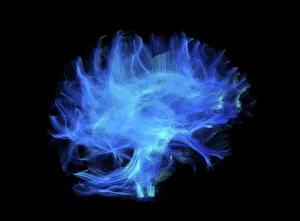

The central nervous system, the intricate network that governs our every thought and movement, is a marvel of complexity. From the delicate cerebellum tissue to the detailed light micrograph capturing its essence, we are reminded of its importance in maintaining balance and coordination. Anatomy comes alive as we explore the human brain from an inferior view. The intricacy of brain fibers is revealed through DTI MRI scans like C017/7099 and C017/7035, showcasing their vital role in transmitting information throughout this extraordinary organ. Artistic renderings bring us closer to understanding the medulla oblongata's significance within the brain. Its portrayal in various artworks allows us to appreciate how it controls essential functions such as breathing and heart rate. As we delve deeper into studying the central nervous system, models of the human brain provide invaluable insights into its structure and organization. Lateral views reveal countless regions responsible for cognition, emotion regulation, sensory perception, and motor control. Microscope slides offer glimpses into nerve cells' intricate architecture—a testament to their ability to transmit electrical signals at lightning speed. Meanwhile, glial stem cell cultures captured under a light microscope remind us of their crucial role in supporting neuronal function. Finally, artistic representations unveil the limbic system's enigmatic nature—an interconnected web responsible for emotions and memory formation. These captivating artworks allow us to visualize this complex network within our brains. Exploring these hints provides a glimpse into the awe-inspiring world of our central nervous system—the very foundation upon which our thoughts, actions, memories reside—reminding us just how remarkable our brains truly are.